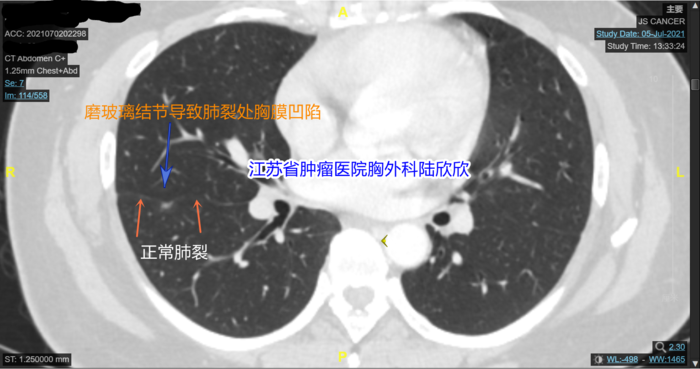

3个月后病人在我们医院复查CT,第二次来挂我的号。我在门诊仔细看它的薄层CT,我说:“在电脑上比手机上看清楚多了。你看,你的磨玻璃结节有明显的胸膜凹陷。你仔细看看,橙色箭头指示的的正常肺裂位置。蓝色箭头指示的是磨玻璃结节将肺裂向结节的方向牵拉,引起肺裂凹陷。这是恶性肺结节的一个重要表现。”

我再观察,发现结节的外形有点不规则,这也是肺癌的一个表现。我测量了磨玻璃结节内部多点的CT值,我说:“你的结节最大CT值是-192,磨玻璃结节周围有环状强化,内部有点状实性成分。所以这个混合磨玻璃结节不可能是原位癌,磨玻璃结节如果是原位癌的话,密度很均匀,一般没有实性成分,形状接近于球形。你的磨玻璃结节密度不均匀,而且有点状实性成分,局部形状不规则,所以可以排除原位癌。那么有没”有可能是微小浸润性腺癌呢?最大CT值我测给你看,大约-192。磨玻璃结节中微小浸润性腺癌的CT值要高一些,一般在-560到-460之间。磨玻璃结节中浸润性腺癌的CT值要更高一些,一般在-460以上,平均值-260左右你的磨玻璃结节最大CT值我刚才测量了,大约-192,CT室医生测量平均CT值-378,所以这个磨玻璃结节应该超过了微小浸润性腺癌的阶段,现在估计已经到了浸润性腺癌的阶段。所以,我的结论和省人民医院和我们医院影像科的看法不一样,他们都认为很可能是微小浸润性腺癌,我认为最可能的诊断是浸润性腺癌。当然也不能排除炎性病变,不过可能性很小。另外,这个结节贴近肺裂胸膜,如果是恶性的磨玻璃结节,比较危险,将来有侵犯胸膜的危险。最好手术切除。手术可以基本上治愈。